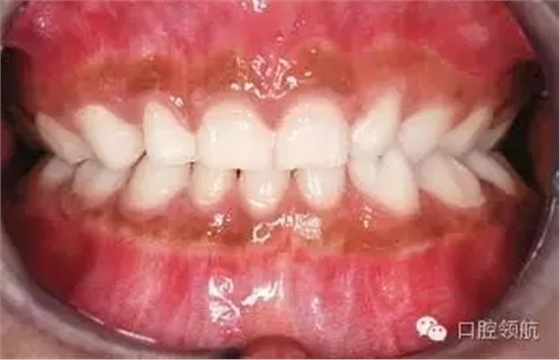

圖2.9中明顯的牙列異常有哪些?

雙側(cè)下頜側(cè)切牙和尖牙移位。

圖2.9

這種異常如何分級(jí)?

牙移位根據(jù)發(fā)生部位、牙齒類型和位置分級(jí)。這種雙側(cè)的移位分級(jí)為Mn.C.I2.

真性移位和假性移位之間的區(qū)別是什么?

真性移位是牙冠和牙根都發(fā)生移位;假性移位只有牙冠發(fā)生移位。